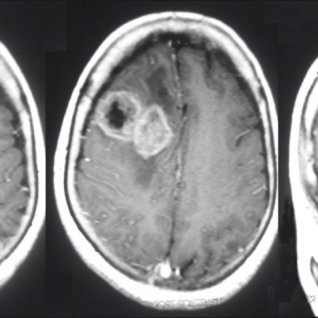

大脑包含三个主要部分:前脑,中脑和后脑。大脑是大脑的较大部分。它位于前脑,分为额叶,顶叶,枕叶和颞叶。额叶负责推理,计划,词性,动作,情绪和解决问题。细胞的异常生长会导致脑瘤在大脑中的任何地方发展。胶质瘤是一种可以影响额叶的脑肿瘤。

脑瘤的症状取决于受影响的大脑部分。由于额叶控制着随意的肌肉运动,因此额叶神经胶质瘤可能会干扰肌肉协调,并导致称为瘫痪的单侧瘫痪。额叶肿瘤的其他症状包括癫痫发作,记忆力减退,性格改变,嗅觉丧失和视力障碍。

胶质瘤的手术目标是大水平地切除肿瘤,同时保留患者的全部功能完整性。目前,在额叶肿瘤切除术中,尽管损害执行功能(EFs)并因此降低生活质量的风险仍然很大,但该目标大部分已实现。

目前,切除范围(EOR)是影响疾病自然进程(生存期,无进展生存期和恶性转化时间)的主要因素之一。脑部绘图(BM)允许根据功能而不是纯粹的解剖边界进行脑部肿瘤切除,从而在保持功能完整性的同时达到近全切除甚至全切除。患者的神经功能完整性的保护可以通过增加映射和手术期间保留神经功能的数量得到确定。切除涉及BM的脑肿瘤是保持患者功能完整性和大水平提高EOR的金标准。目前,BM合适地帮助保留了几种运动,实践和语言功能。